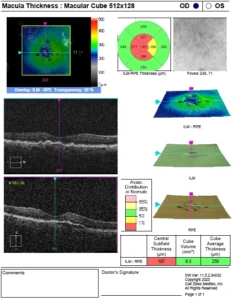

- OPTICAL COHERENCE TOMOGRAPHY (OCT)

OCT showing normal foveal contour in both eyes

Optical coherence tomography is a non-invasive imaging test, which uses light waves to take cross-section pictures of patients’ retina.

With OCT, the retina specialist can see each of the retina’s distinctive layers. This allows mapping and measuring retinal thickness. These measurements help with diagnosis. OCT also guides treatment for retinal diseases, like age-related macular degeneration (AMD), diabetic eye disease, and macular oedema.

The retina specialist may or may not put dilating eye drops. These drops widen the pupil and make it easier to examine the retina.

The patient sits in front of the OCT machine and rests their head and chin on a support to keep them motionless. The retina specialist then scans the eye without touching it. Scanning takes about 5 to 10 minutes.

OCT is often used to evaluate disorders of the optic nerve as well. The OCT exam helps the retina specialist see changes to the fibres of the optic nerve. For example, it can detect changes caused by glaucoma.

OCT relies on light waves. It cannot be used with conditions that interfere with light passing through the eye. These conditions include dense cataracts or significant bleeding in the vitreous.